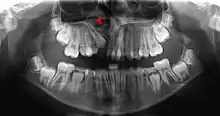

This X-ray film reveals some bone loss on the right side of the mandible. The associated teeth exhibit poor crown-to-root ratios and may be subject to secondary occlusal trauma.

Bone is lost through the process of resorption which involves osteoclasts breaking down the hard tissue of bone. A key indication of resorption is when scalloped erosion occurs. This is also known as Howship's lacuna.[18] The resorption phase lasts as long as the lifespan of the osteoclast which is around 8 to 10 days. After this resorption phase, the osteoclast can continue resorbing surfaces in another cycle or carry out apoptosis. A repair phase follows the resorption phase which lasts over 3 months. In patients with periodontal disease, inflammation lasts longer and during the repair phase, resorption may override any bone formation. This results in a net loss of alveolar bone.[19]